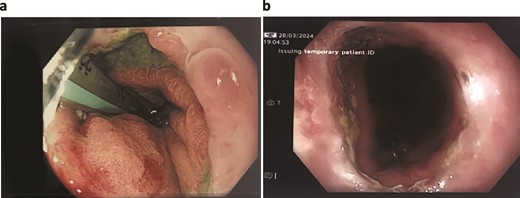

Unfortunately, the patient developed respiratory sepsis and a small bowel obstruction, requiring ICU readmission and intubation. An exploratory laparotomy on postoperative day 5 showed no evidence of ischemia or perforation. A subsequent OGD on postoperative day 8 revealed a 20% staple line defect (Fig. 4a), leading to VACStent and right chest drain insertion.

Patient Four: (a) Before VACStent insertion, showing the oesophageal defect. (b) After VACStent treatment, demonstrating successful defect closure.

Following the removal of the VACStent on postoperative day 13 (Fig. 4b), the patient underwent a prolonged antibiotic course and received dietician support for jejunal feedings. Despite complications, including unsuccessful extubation and bilateral pleural effusions, the patient gradually improved with comprehensive care. A drain was placed on postoperative day 23 to address chest wall collections, and the patient was weaned off the tracheostomy by day 31. The patient continued to recover, managed hypertension, and was discharged home on day 82, with various supports in place and a follow-up scheduled in the clinic.